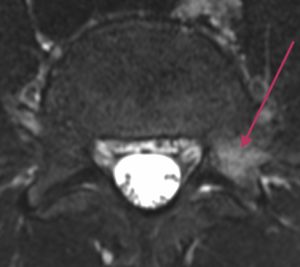

Lannerangan poikkileikkaus 1

Lannerangan aksiaalikuva (poikkileikkaus).

Magneettikuvauksen avulla voidaan nähdä selkäydinkanavan tilavuus ja hermojuurten vapaa tila. Poikkileikkauskuvista (aksiaalitaso) voidaan luotettavasti todeta mahdolliset hermopinnetilat, joita esimerkiksi välilevyn pullistuma voi aiheuttaa.